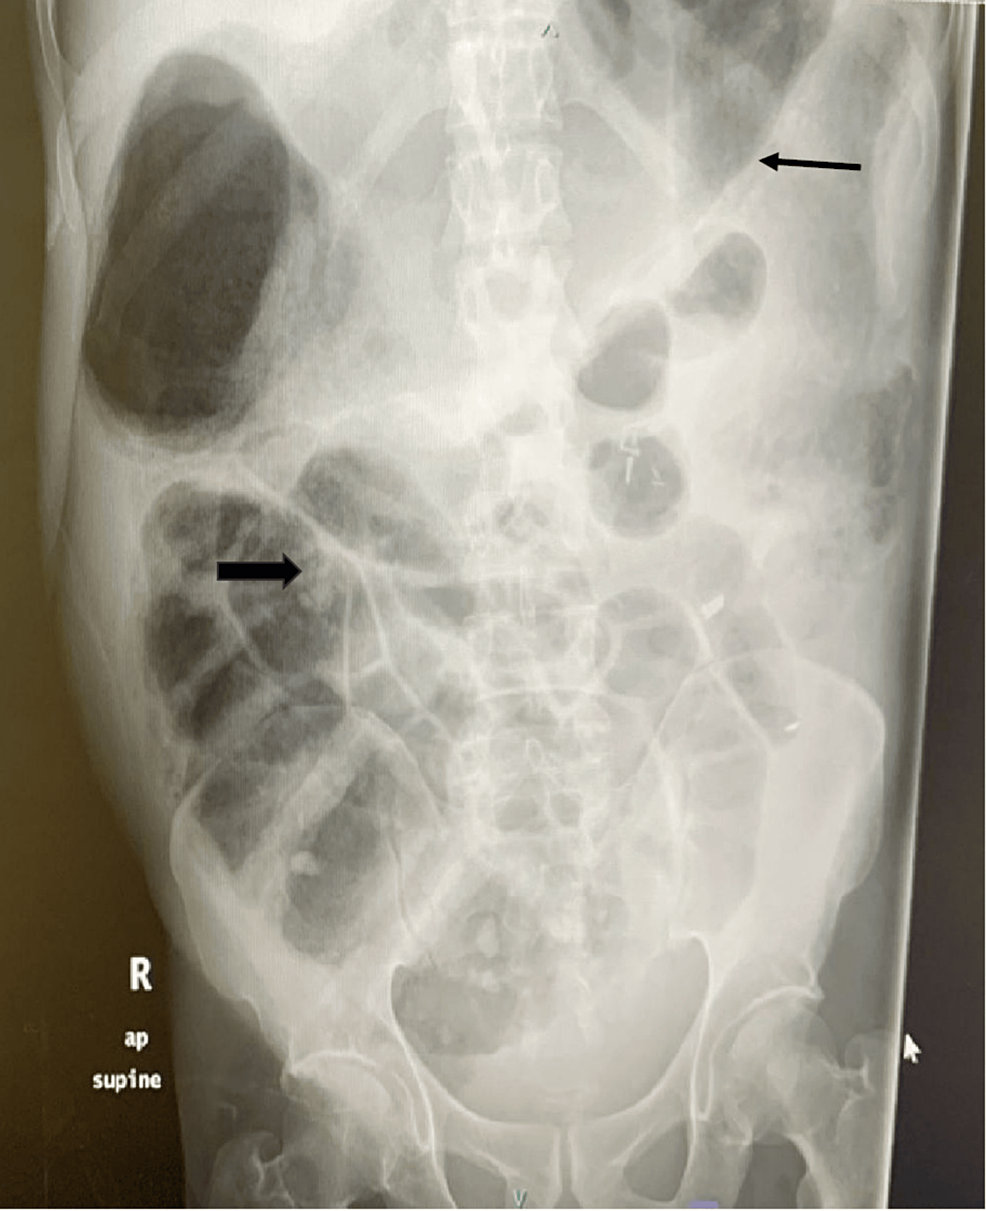

Endoscopic Decompression For Acute Colonic Pseudo-Obstruction . acute colonic distension is a medical emergency with high morbidity. On completion of this article, the reader should be able to review diagnostic testing confirming diagnosis of acute. this experience demonstrates that colonoscopic decompression with decompression tube placement is safe. patients that fail medical therapy may benefit from colonoscopic decompression or surgical decompression. efficacy, safety, and outcome of endoscopic decompression was assessed.

On completion of this article, the reader should be able to review diagnostic testing confirming diagnosis of acute. acute colonic distension is a medical emergency with high morbidity. this experience demonstrates that colonoscopic decompression with decompression tube placement is safe. patients that fail medical therapy may benefit from colonoscopic decompression or surgical decompression. efficacy, safety, and outcome of endoscopic decompression was assessed.